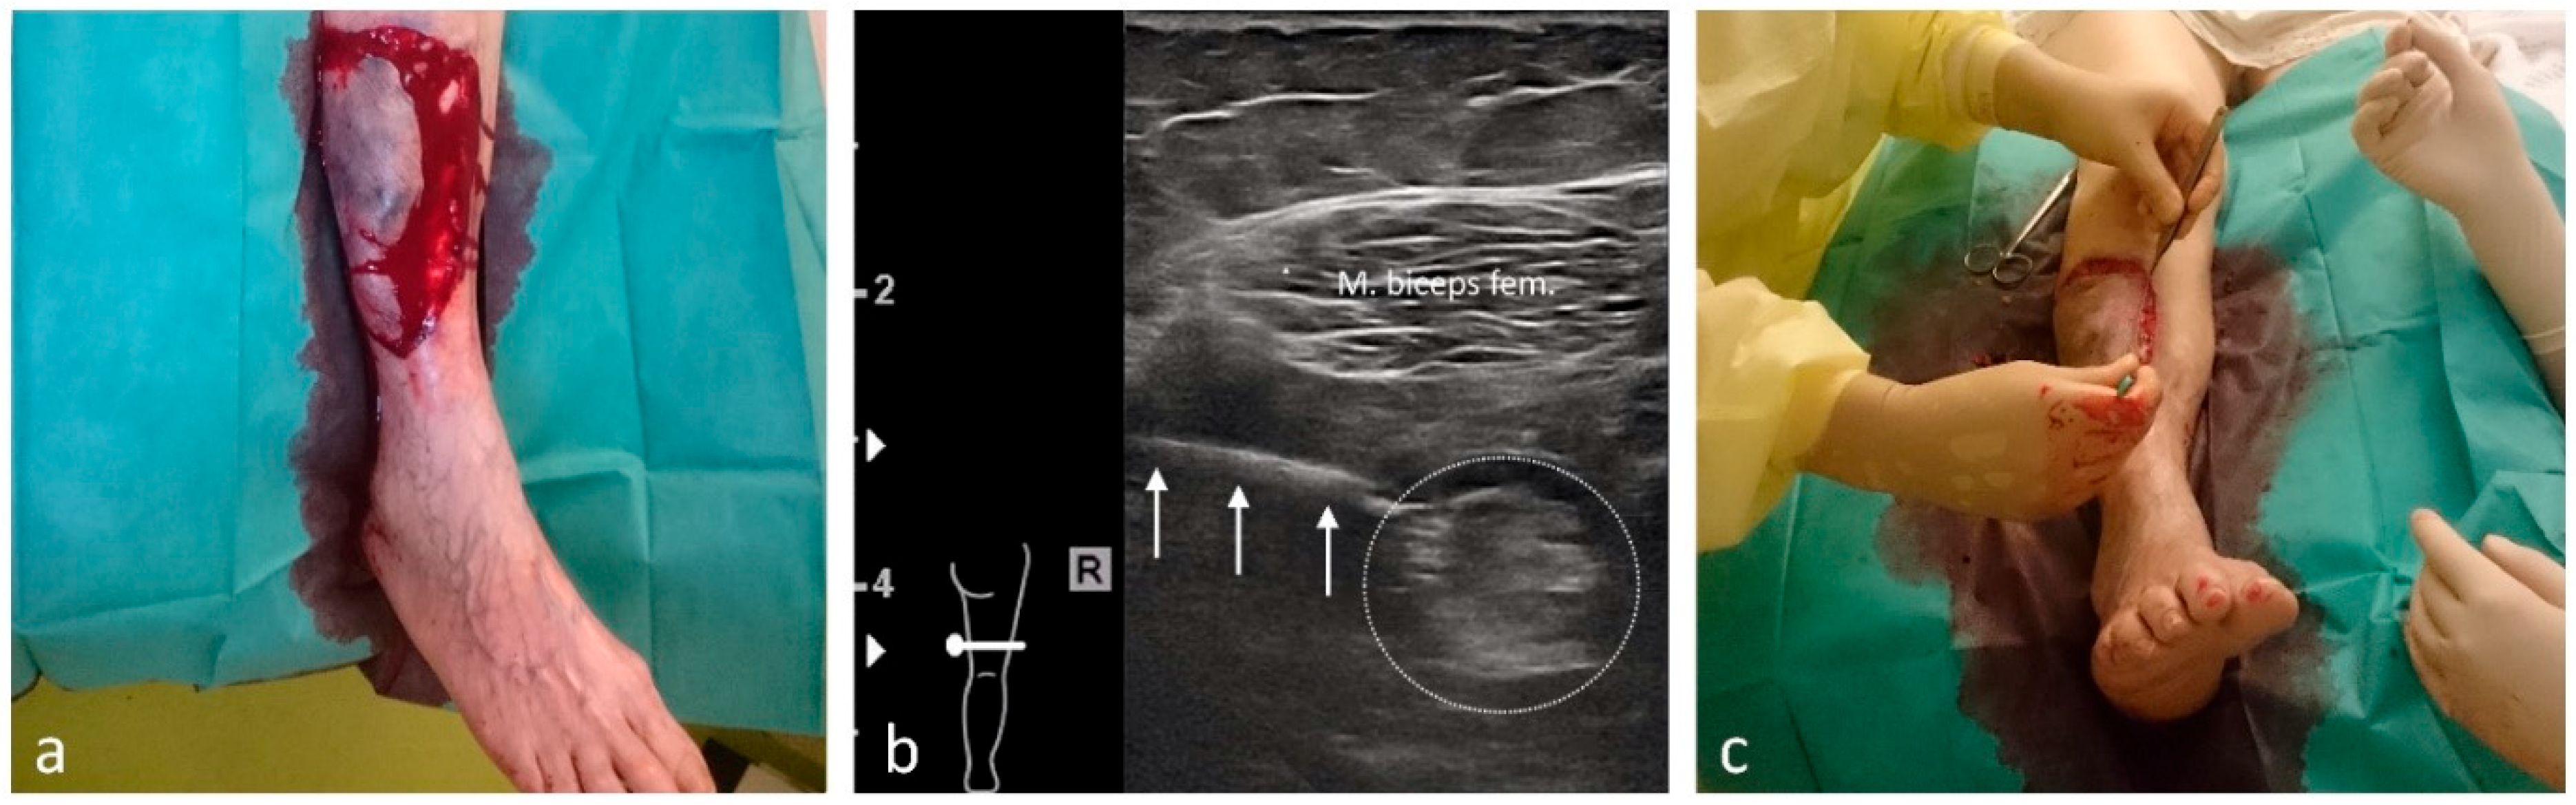

| Femoral shaft/distal femur | 25 | Femoral and obturator nerves/10 each |

| Lower leg | 3 | Femoral and sciatic nerves/10 each |

| Ankle and foot | 34 | Femoral and sciatic nerves/10 each |